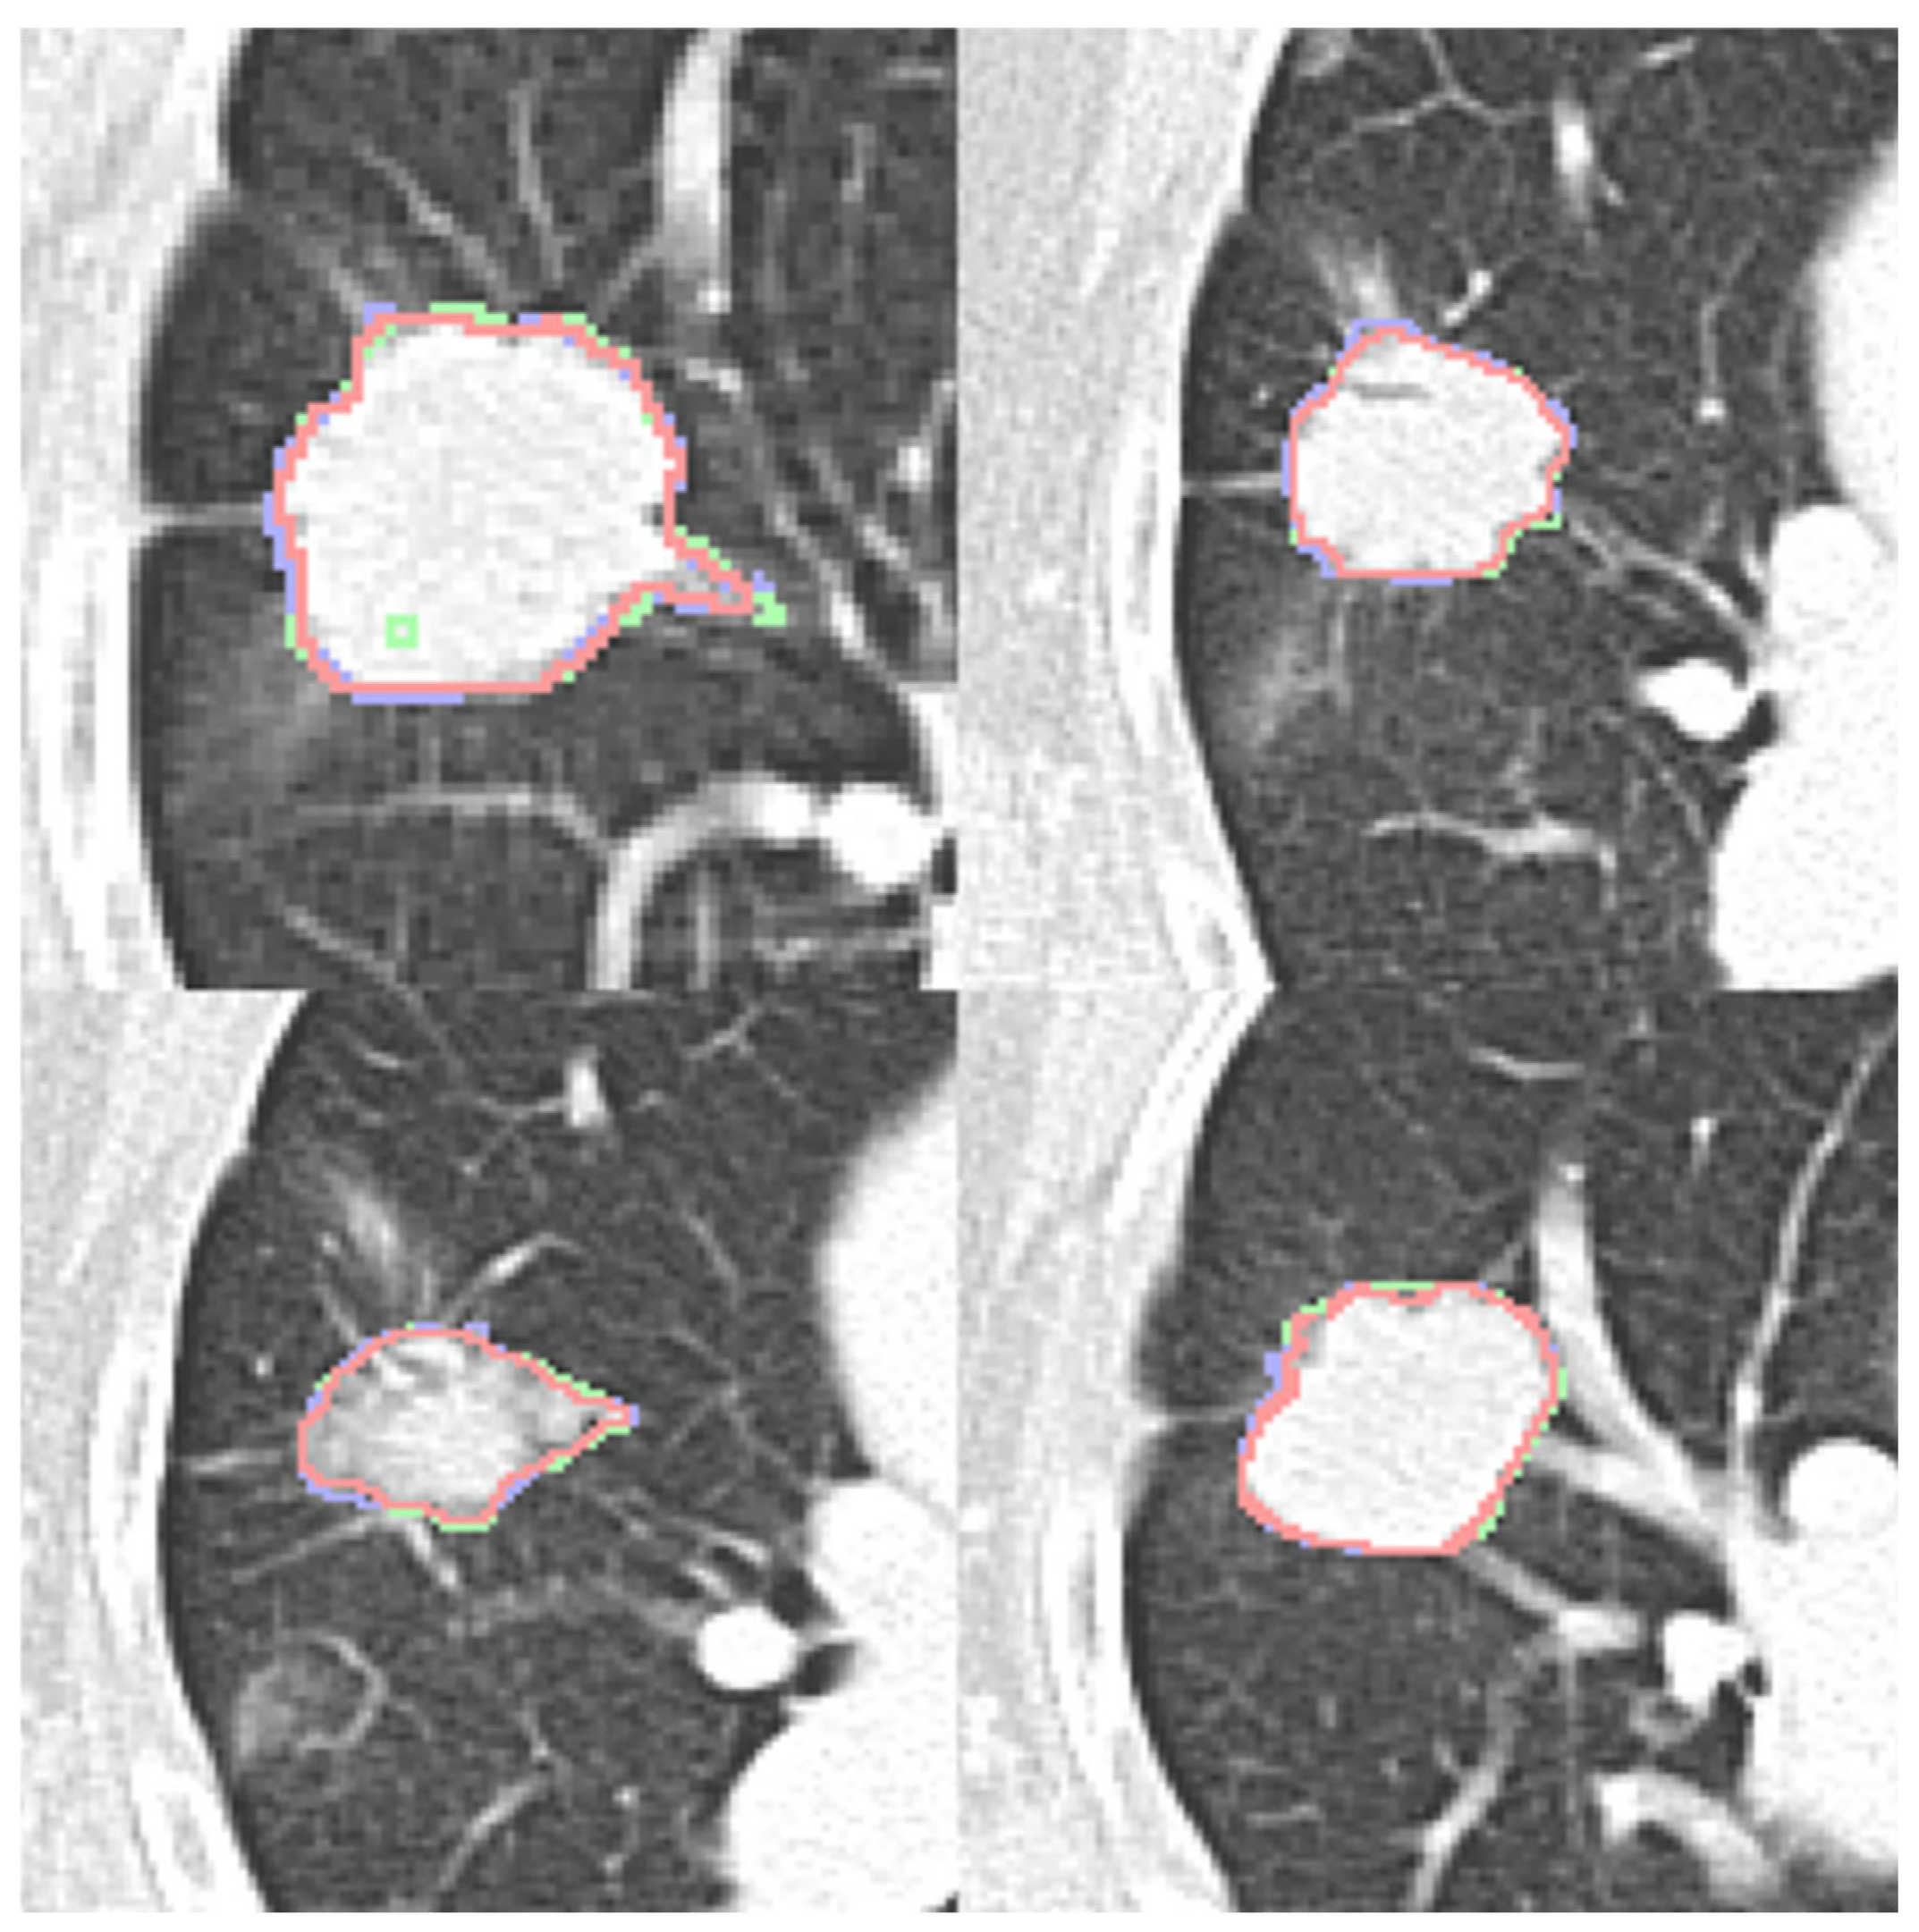

Four expert contours exist in the LIDC-IDRI dataset and two in the dataset (b). Four qualitative contour fusion results are demonstrated in Figure 3. Three contours are superimposed on the raw patch. The blue and green colors represent two manual contours, while the red color indicates the fusion result. Minor inconsistencies are observable. Notably, there is a manual error in Figure 3 (top left), represented in green, where an extra point is erroneously included. However, the fusion result does not reflect this mistake. The proposed contour fusion technique effectively mitigates sharp variations exhibited by both experts, such as protrusions or indentations, thereby addressing the gaps left by incomplete annotations.

Figure 3. Four contour fusion results. Three contours are superimposed on a raw patch. The blue and green lines illustrate contours meticulously delineated by two human experts. The red line represents the contour fusion, which aligns the nodule areas from the two experts, providing a refined depiction.